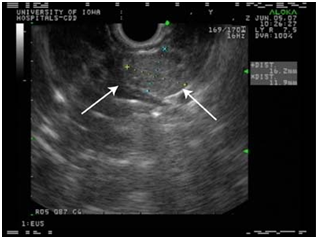

Endoscopic ultrasound

EUS allows the positioning of a high frequency (7.5-10 MHz) transducer in close proximity to the pancreas and lesions as small as 5 mm as well as tumors located in the bowel can be detected.

Although there is a potential "blind-spot" at the splenic hilum, a high sensitivity has been obtained. A recent single-centre prospective study showed a sensitivity of 93% and a specificity of 95% in localization of intra-pancreatic lesions. EUS could detect all tumors visualized by every other conventional technique, thus questioning the need for the rest imaging modalities (Figure 6–8).44–48

Figure 8 Linear endoscopic ultrasound image of a neuroendocrine tumor of the pancreas (insulinoma) undergoing fine needle aspiration. Note the rim-enhancing mass in the tail. 43